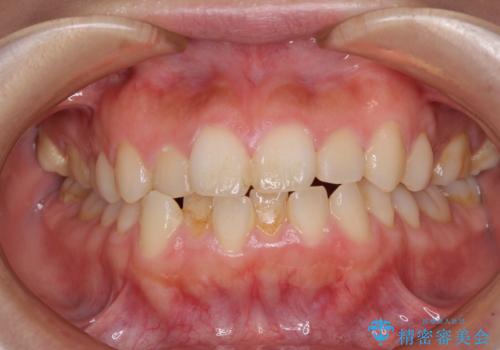

口が閉じられない ワイヤー装置による矯正治療

- 前歯が突出しているために口が閉じられないとのことで来院された患者様です。

上下ともに顎が小さく、歯列が前方に突き出していたため、上下左右の第一小臼歯4本を抜歯し、口元の突出感を改善していくこととしました。